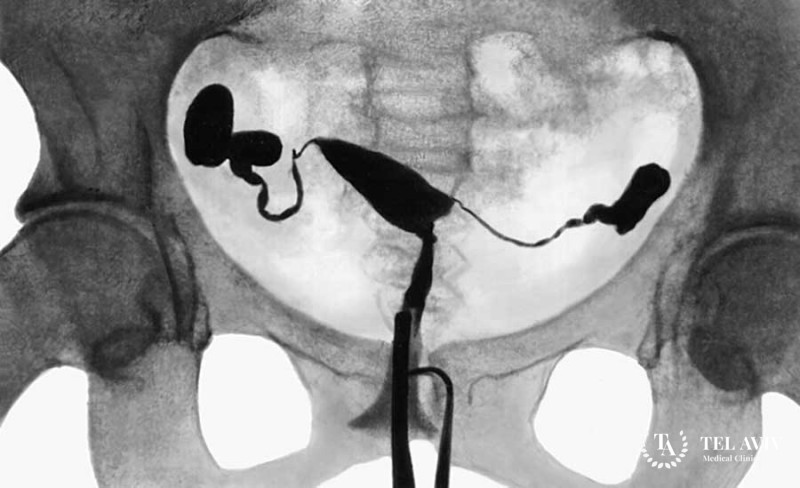

Гистеросальпингография (ГСГ) маточных труб – это исследование проходимости труб, которое выполняется с помощью рентгена или УЗИ и контраста. Данная методика является ключевой для обнаружения заболеваний матки. По сравнению с УЗИ, она занимается почетное место среди обследования мочеполовой системы женщин.

Перед проведением обследования пациент сдает анализ крови и мочи, берется мазок из влагалища, удаляются лишние волосы с половых органов, делается очистительная клизма. С собой необходимо иметь карточку, данные предыдущих исследований, сменную обувь. Врач берет с собой необходимый инструмент. Затем обрабатывает половые органы антисептиком. После этого вводит специальный препарат и проводит рентгенограмму.